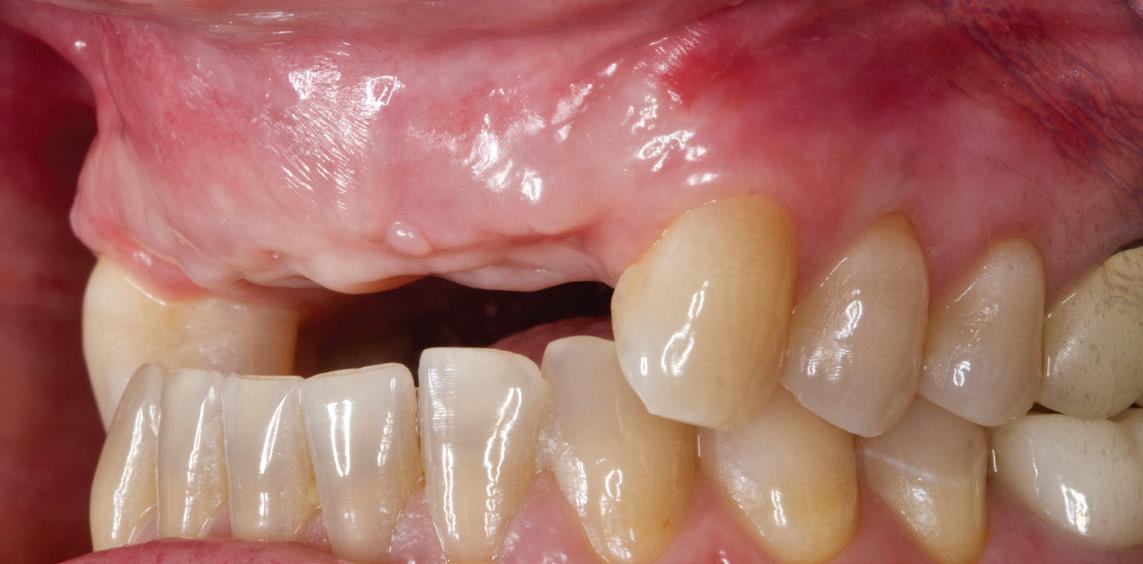

Un pacient caucazian în vârstă de 77 ani s-a prezentat la clinica autorului după cinci ani în care nu a fost la niciun control stomatologic. Examinarea clinică a arătat o pierdere semnificativă de os, parodontită cronică și multiple edentații care au destabilizat ocluzia. Pacientul a raportat sensibilitate la rece la nivelul primului molar drept inferior nr. 46, în special la ingerarea de lichide reci. Radiografia periapicală a confirmat constatările examenului clinic; în

plus, s-a detectat și prezența unei carii radiculare la nivelul rădăcinii distale a aceluiași molar, cu răspuns pozitiv la testul de sensibilitate (fig. 1-2).

Planul de tratament a început cu accent pe restabilirea sănătății parodontale. Într-o ședință ulterioară, odată cu îmbunătățirea stării parodonțiului, s-a efectuat restaurarea molarului nr. 46. Sub anestezie la Spina Spix pe partea dreaptă și

Figurile:

1. Situația clinică inițială.

2. Radiografia inițială.

3. Cavitate de clasa a II-a preparată.

4. Septomatrix pe poziție.

5. Cavitatea profundă.

izolarea cu digă de cauciuc, restaurarea din amalgam a fost îndepărtată complet și s-a obținut accesul la cavitatea carioasă (fig. 3-5). În ciuda proximității față de țesutul pulpar, nu a avut loc nicio expunere, iar cavitatea de clasa a II-a a fost restaurată complet cu Biodentine™ (fig. 6-8).